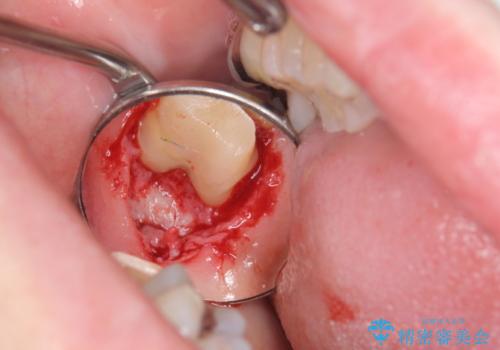

- 銀歯をやりかえたいが他院で抜歯と言われセカンドオピニオンで来院。適合の悪い被せ物が入っており、まずは古い材料、虫歯をとり保存可能か確かめる必要があり、拡大鏡下で全て取り除いたら歯質が歯茎の中まで虫歯がありました。このまま無理やり型取りをして被せ物を作っても不適合な被せ物が入る可能性が高いため歯茎を切り取る手術(ディスタルウェッジ)を行いました。そして再根管治療を行いゴールドの被せ物で治療を行いました。

- PGAクラウン・仮歯 13.2万円×2 精密根管治療(リトリートメント)・コア 16.5万円×2 ディスタルウェッジ 1万円費用は治療当時の料金となります